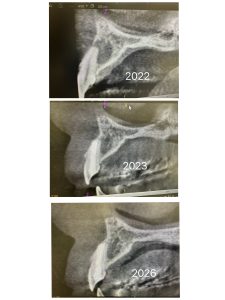

根管治療MTA.ヤグレーザー、ソケットリフトインプラント2本、ジルコニア9本

根尖から遠方より段々と骨化している

大きな病巣は5年位経過を追うと良い

楽しみだ💪